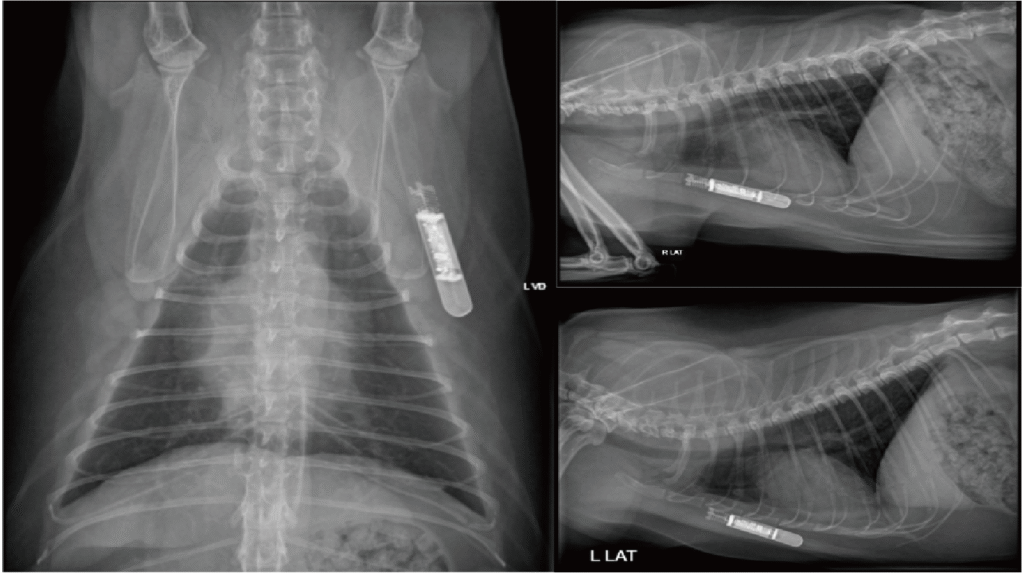

2025/1/7 植入 Medtronic Reveal LINQ™(圖 2);1/8 起 ICM 陸續自動記錄到第二級與三級 AV block 交替,無超過 3 秒的停搏(pause)且無臨床症狀;期間 24 小時平均心率多在 125–158 bpm,最高可達 333 bpm。於 2025/1/15 記錄到一長達10秒的高度AV block,但家屬未觀察到症狀(圖 3)。約 3 月中,心率轉為永久性三級 AV block,整日平均心率下降至 70–75 bpm,家屬未觀察到任何臨床症狀。由於整日平均心率逐漸下降至60-65 bpm,雖無臨床症狀,於5/1 起家屬同意投予 theophylline 9.124 mg/kg PO q12h 與 cilostazol 9.884 mg/kg PO q12h,24 小時平均心率於服藥後一度回升至 80–90 bpm,惟約一個月後逐漸回落;6 月起即使持續服藥,平均心率僅 60–65 bpm。8/9 15:03 家屬觀察到叫聲後癱軟,ICM 同步紀錄大於 5 秒心搏停止(圖 4);8/10 回院評估後建議置入人工節律器,並於同日檢測 theophylline濃度 18.9 μg/mL,顯示已無進一步調高劑量的空間。8/26 經腹腔橫膈膜通道放置單腔心外膜節律器(VVIR)(圖 5);植入時檢測內在心率僅 50 bpm。術後門診檢查顯示 >99% 依賴節律器驅動,臨床症狀消失,活動量與睡眠品質顯著改善。